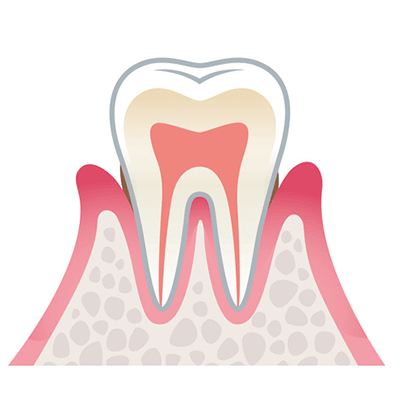

1.軽度歯周病

歯ぐきに炎症が起こり、歯と歯ぐきの間にある歯周ポケットが深くなります。

痛みはほとんどありませんが、歯みがき時に出血することがあります。

1.軽度歯周病

歯ぐきに炎症が起こり、歯と歯ぐきの間にある歯周ポケットが深くなります。

痛みはほとんどありませんが、歯みがき時に出血することがあります。